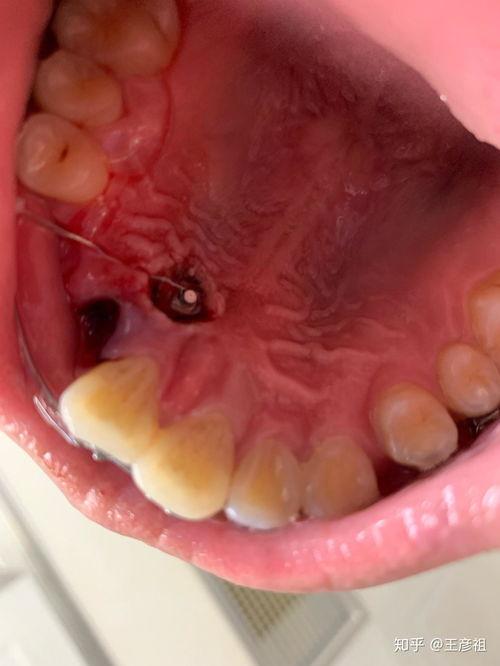

首先,我们要明白,“成人埋伏牙”这个词汇其实是指成年人牙齿生长过程中出现的一种异常情况。简单来说,就是成年后牙齿突然长出来,就像是在牙床里埋伏了一样。这种牙齿问题在网络上引起了广泛关注,很多人通过视频来了解和解决这一问题。

在各大视频平台上,搜索“成人埋伏牙视频”,你会发现各种各样关于这个话题的内容。有的视频详细介绍了埋伏牙的形成原因、症状表现以及治疗方法;有的视频则是分享患者亲身经历,讲述他们如何与埋伏牙作斗争;还有一些视频则是幽默搞笑,用夸张的手法展示埋伏牙的“威力”。

3. 拔除治疗:如果埋伏牙影响口腔健康,可以考虑拔除。

4. 手术治疗:在必要时,可进行手术治疗,将埋伏牙移至正常位置。